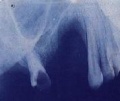

El granuloma reparativo central de células gigantes, crece en niños(as) o adultos jóvenes y tiene predilección por el sexo femenino; después del traumatismo se origina una etapa asintomática, hasta que se organiza la lesión, con posterioridad el primer signo que se manifiesta es la movilidad o migración dentaria, con abultamiento de las corticales, tanto por el vestíbulo bucal como por el palatino o lingual, esto depende del lugar donde se localice la proliferación, no hay dolor. El GRCCG, es una lesión propia de los huesos maxilares, con predominio en la mandíbula; es una entidad relativamente frecuente en los niños(as). Radiográficamente la destrucción ósea que ocasiona es inquietante y fácilmente confundible con un proceso neoplásico maligno; los bordes de la imagen radiolúcida son irregulares y esta no es patognomónica del proceso. El calcio y el fósforo sérico, así como la fosfatasa alcalina son normales; esto es algo que lo diferencia de su similar del hiperparatiroidismo.